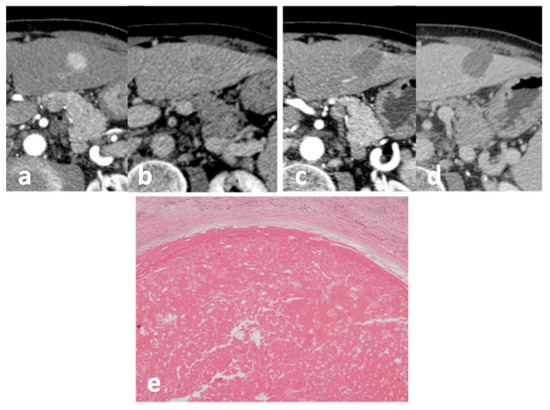

| One-Month Post Procedural Imaging Evaluation | |||

| Complete response | 30/36 (83.3%) | ||

| Viable disease | 6/36 (16.7%) | ||

| Pathological Data | |||

| Complete necrosis | 28/36 (77.8%) | ||

| Partial necrosis | 8/36 (22.2%) | ||